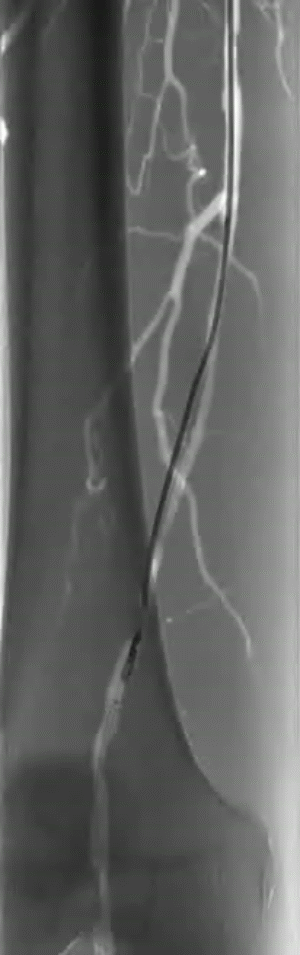

术前CTA:左侧股浅动脉重度钙化,双髂动脉重度狭窄。

图片

手术策略:DA+DCB